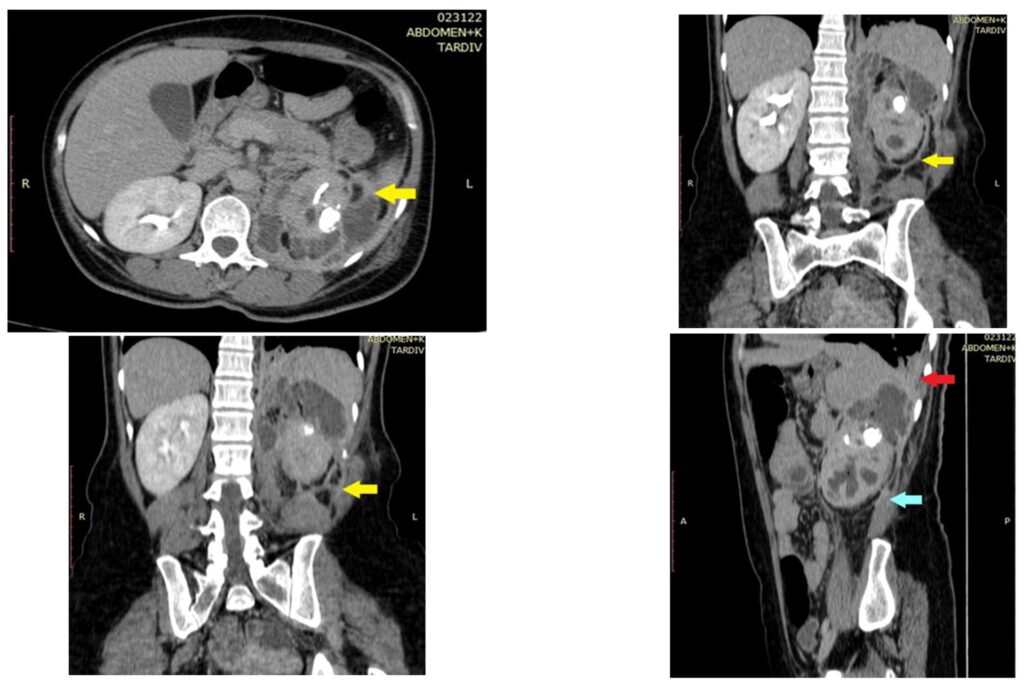

- Nyrerne (Xanthogranulomatøs Pyelonefritis): Ofte forbundet med kroniske urinvejsinfektioner og nyresten, der blokerer urinstrømmen. Inflammationen kan ødelægge nyrevævet og få det til at ligne en nyretumor.

Den største kliniske udfordring ved den xanthogranulomatøse proces er dens evne til at efterligne en ondartet tumor. På billeddiagnostiske undersøgelser som CT- eller MR-scanninger kan XP fremstå som en invasiv, solid masse, der er svær at skelne fra kræft. Dette skaber en betydelig diagnostisk udfordring.

Derfor er den endelige diagnose næsten altid afhængig af en vævsprøve (biopsi). Når vævet undersøges under et mikroskop af en patolog, kan de karakteristiske skummende makrofager, blandet med andre inflammatoriske celler og tegn på nekrose, bekræfte, at der er tale om en godartet inflammatorisk proces og ikke kræft. Denne afklaring er afgørende for at undgå unødvendigt aggressive behandlinger, som f.eks. omfattende kirurgi eller kemoterapi.